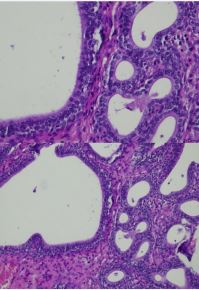

Pathologically, tumor formation is characterized by an adenomatous tubular proliferation made up of elements of variable size and shape, sometimes distended or even cystic. Their epithelium does not show cytonuclear atypia and the interstitial tissue is inflammatory congestive. The base of the tumor bed has an epithelium with a focus of squamous metaplasia (Figures 2,3).